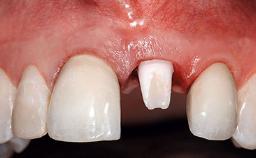

A 49-year-old female patient was referred for implant therapy to replace the upper right central incisor (tooth 11). The tooth had been assessed by an endodontist who diagnosed a vertical fracture of the root. The tooth had a hopeless prognosis and needed to be extracted. The patient was healthy and was not taking any medications. She was allergic to penicillin. The patient had high esthetic demands but her expectations were realistic. The extraoral examination revealed no facial asymmetries. The right temporomandibular joint demonstrated an opening click but was otherwise asymptomatic. The lip line was high with a significant gingival display.